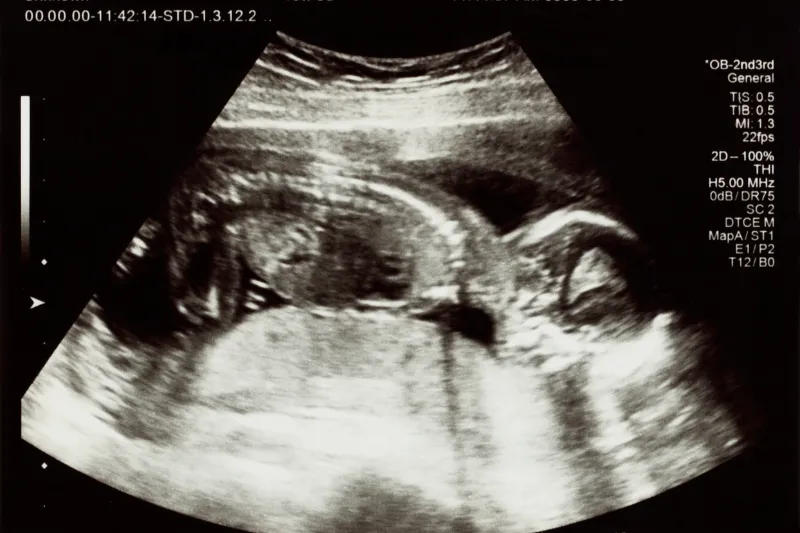

Diferencias Entre Ecografías: 2D, 3D, 4D y 5D

| Ecografía 2D | Imagen plana en blanco y negro | Todo el embarazo |

Eco Morfológico: ¿Para Qué Sirve y Cuándo Hacerlo?

¿Qué es el Eco Morfológico?

El eco morfológico es un estudio detallado que evalúa:

- Anatomía fetal completa

- Medidas craneales, abdominales y de fémur

- Estructura de órganos vitales

- Placenta y líquido amniótico